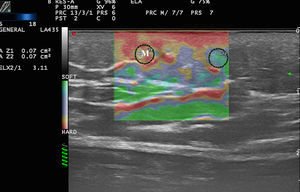

En el caso del melanoma, en el estudio piloto de Botar et al.26 —que incluía 42 melanomas en 39 pacientes— estudiaron la SE y la vascularización mediante Doppler color de las lesiones.

Los melanomas presentaron hipervascularización con múltiples pedículos vasculares y mayor dureza en la SE que la piel adyacente. Así mismo, las lesiones más vascularizadas presentaron una mayor dureza.

Es bien conocido en la literatura que existe una correlación entre la neovascularización del melanoma y su pronóstico27,28, por lo tanto, la dureza lesional podría ser un factor pronóstico en el melanoma29.